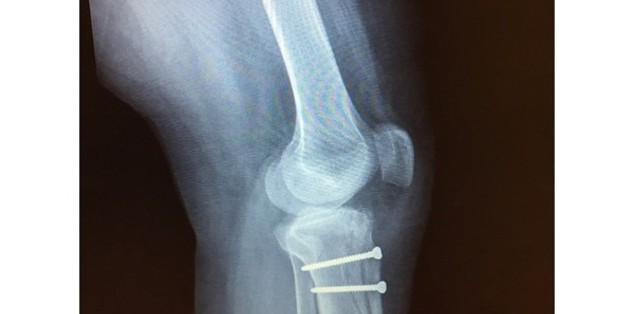

From that very first appointment I knew that I had made the best decision of my life. After examination, he realized that my knee cap wasn't sitting in the proper place, which explained all of my pain, catching, grinding. So a week later, he had me in for surgery at which time I had a lateral release on July 24th, 2014. Unfortunately, the procedure didn't bring the result that we had hoped for. Though my knee cap had come back down where it belonged, I still had continued pain. To try to buy time before going i n for another surgery, Dr. Tjoumakaris tried a series of the OrthoVisc injections, which did buy us about a month or so.

A month after the injections, I was back in his office without relief so he proceeded to order a bone scan. I had my scan and had an appointment the following week to discuss the results. As soon as he came in the room he knew what he was going to tell me, so he looked at the scans and came right out and said I would need a Fulkerson Osteotomy with medial reefing if I wanted any chance of pain relief. He had said it wasn't guaranteed, but at this point it was our only option.

So, even though I was scared to death to go under the knife yet again, I trusted him, and I knew that this would be the end of the road. On January 8th, 2015 I had my reconstructive surgery. Now, 14 weeks later, I feel absolutely incredible. It's as if I've been given a new opportunity to live my life. I remember Dr. Tjoumakaris had said that it was a teamwork between him and I, and he couldn't have been anymore right. He has been there every step of the way and thank you will never be enough for everything he's done.